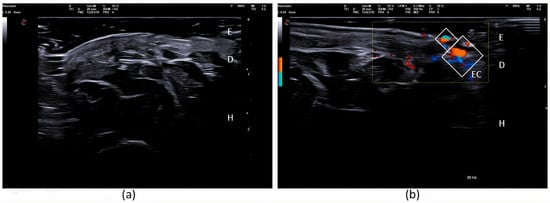

2. Case Report

3. Discussion